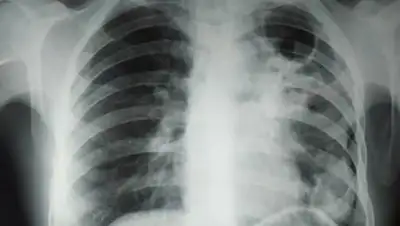

Клинически туберкулез ничем не отличается от коронавирусной инфекции.

При туберкулезе, как и при COVID-19 также поражаются легкие, бывают признаки кашля, температуры, одышки, в некоторых случаях кровохарканье. Разницу дообследования можно узнать только по анализам: по забору мокроты и по ПЦР тесту.

КВИ — это заболевание вирусного происхождения, возбудителем туберкулеза является бактерия, т.е при COVID-19 легкие поражает вирус, то при туберкулезе - бактерии.

Туберкулез можно выявить 4 методами исследований: бактериологическим (микроскопическое исследование материала и культуральное исследование, т.е посев материала), молекулярно-генетическим экспресс методом (GeneXpert, Хайн-тест), рентгенологическим и туберкулинодиагностикой (проба Манту).